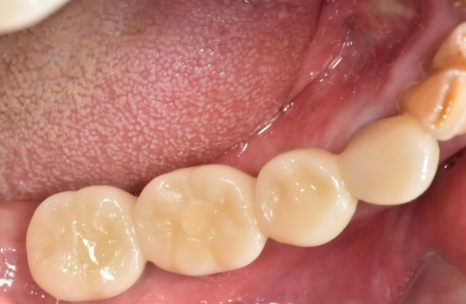

3개월의 기다림 끝에,

양쪽 어금니 모두

250905

흔들리고 냄새나던 브릿지 대신,

단단하게 고정된 임플란트가 생기니

무엇보다 '씹는 맛'이 다르다고 하십니다.

250403 (전) 250905 (후)